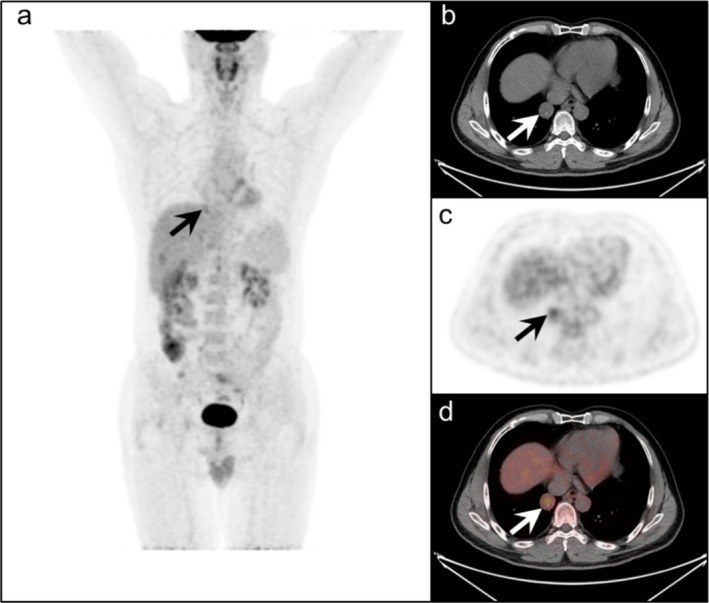

Results: The 46 tumors were randomly distributed in each lobe of both lungs. The mean maximum diameter of these lesions was 2.2 cm (range: 0.6 to 6.5 cm). The mean SUVmax was 2.96 ± 1.88 (median: 2.69, range: 0-9.02). Thirty-three cases were categorized as mild to moderate FDG uptake, eleven cases were categorized as intense FDG uptake, and no FDG uptake was observed in the remaining two cases of the lesions qualitatively evaluated. The SUVmax of the PSP showed a positive correlation with the maximum diameter of the tumors (R = 0.493, R2 = 0.258, and p < 0.001). SUVmean (R = 0.500, R2 = 0.259, p < 0.001), SUVpeak (R = 0.553, R2 = 0.324, p < 0.001), MTV (R = 0.773, R2 = 0.592, p < 0.001) and TLG (R = 0.800, R2 = 0.654, p < 0.001) were positively correlated with the maximum diameter of the tumor.

Conclusion: In our study, statistically significant positive correlations were found between SUVmax, SUVmean, SUVpeak, MTV, and TLG and the maximum diameter of PSP. We found that the maximum diameter of the tumor is associated with an increase in FDG uptake in PSP, reflecting a potential correlation between lesion diameter and PET metabolic parameters, indicating a link between structural features and metabolic activity.